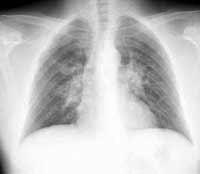

Безусловно, такие морфологические изменения, как число очагов, форма, размеры, интенсивность, структура, контуры, хорошо определяются, так как пространственное разрешение с учетом проекционного увеличения изображения составляет 0,5 мм (1 пара линий/мм.) (Рис. 1, 2).

Рис. 2. Определяется увеличение бронхопульмональных лимфоузлов, интерстициальные и очаговоподобные изменения, морфологическим субстратом которых являются саркоидозные гранулемы.